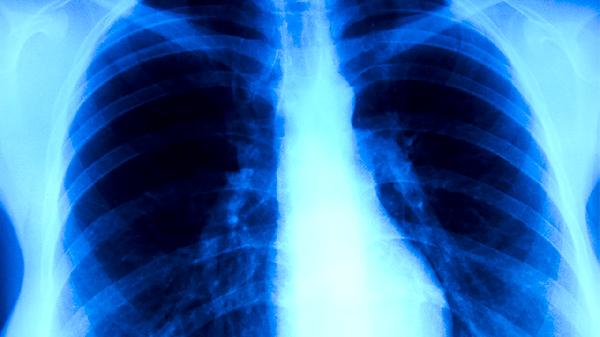

紫龙金片是一种中成药,主要成分包括黄芪、当归、白花蛇舌草等中药材,具有益气养血、清热解毒的功效。在肺癌治疗中,紫龙金片可能有助于改善患者免疫功能,减轻放化疗引起的恶心呕吐、乏力等不良反应。部分临床研究显示,该药物可能对抑制肿瘤生长、延长生存期有一定帮助,但需配合手术、放疗或化疗等主要治疗手段。

需要注意的是,紫龙金片并非肺癌的特效药,其疗效尚未获得大规模临床研究充分证实。某些患者可能出现药物过敏、胃肠不适等不良反应,合并使用其他抗肿瘤药物时可能存在相互作用。晚期肺癌患者或存在严重肝肾功能障碍者需谨慎使用,妊娠期妇女禁用。